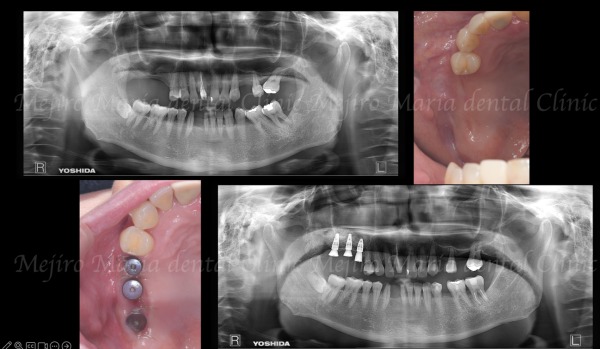

【症例】サイナスリフトで骨を増やし、奥歯の支えを回復したインプラント治療

• ビフォーアフター|【症例】抜歯後に大きく失った骨をGBR(骨造成)で再建し、清掃性と長期安定性を確保したインプラント治療|目白マリア歯科

【症例】抜歯後に大きく失った骨をGBR(骨造成)で再建し、清掃性と長期安定性を確保したインプラント治療